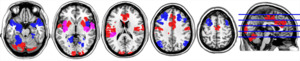

The two FNs contain key regions that play roles in incentive sensitization, reward valuation, and executive function.2,33 For FN1, the ROIs in the most posterior area of the brain are in the visual cortex, while the nodes in the more anterior locations occupy lateral motor and somatosensory regions, the anterior cingulate, and the posterior insula. The nodes located in the inferior posterior aspect of the brain occupy the cerebellum. For FN2, the ROIs located in the superior aspect of the brain are part of the attention-processing circuit. The nodes in the inferior aspect of the brain localize to the amygdala, temporal pole, hippocampus, fusiform gyrus, and inferior insula. Figure 2 provides a visualization of FN1 and FN2. For a complete list of Shen atlas regions belonging to each FN, please see the supplementary appendix.

The community membership of each of the 5 states is shown in Figure 5. There were no states that exhibited community structure with FN1 and FN2 each in a single community, as all states had more than 2 communities. State 1 had three communities while states 2-5 each had four communities. The regions encompassed by FN1 and FN2 broke into several meaningful clusters such that there was an overall pattern that emerged across states. This pattern was such that the lateral sensorimotor regions and cingulate regions (likely motor planning) from FN1 (green community) and the limbic regions from FN 2 (red community) were typically each in their own community that may or may not include other state-distinguishing regions. The lateral frontal and parietal regions from FN2 were typically separate from the sensorimotor or limbic areas in a single community (blue community) that also included cerebellum and visual cortex that are part of FN1. When the frontal and parietal were not in the same community, they exhibited an anterior/posterior split forming a unique module primarily containing the frontal regions (but see below). The insula turned out to be one of the most interesting regions distinguishing the different states. It exhibited the most fickle behavior as it changed community allegiance quite dramatically. It was totally aligned with either the sensorimotor or the limbic, or split with more posterior aspects being aligned with the sensorimotor areas and the inferior/anterior aspects being with the limbic areas.

States 1 and 3 are the two states that the successful weight-loss group spent more time in, on average, compared to the unsuccessful weight-loss group. In state 1, sensorimotor and basal ganglia regions are in a module together (all FN1 regions). No portions of the insula were in the module with the sensorimotor regions. In contrast, state 3 had the sensorimotor and dorsal posterior insula (mostly FN1 regions) form a module. Lastly, in both states 1 and 3, the insula and limbic structures are well integrated (which consist of the shared FN1 and FN2 regions). In state 1 it is the entire insula with the limbic regions but in state 3 it is the anterior inferior portion of the insula. Figure 6 demonstrates that states 1 and 3 are characterized by strong FN1 connections bilateral between the motor areas (state 1) with additional connections between the motor area and dorsal posterior insula (state 3). These two states are also characterized by positive connectivity between insula and limbic structures. The split of the frontoparietal module in state 3 is noted by the absence of long-range positive connections between frontal and parietal cortex. This is most evident when comparing the sagittal images for states 1 and 3.

States 2 and 4 are the two states that the unsuccessful weight-loss group spent more time in, on average, compared to the successful weight-loss group. State 2 exhibits a striking difference from all other states. In this state, the limbic system (part of FN2) is in a module by itself. This is the only state where this was observed. Additionally, the sensorimotor regions are in a module containing the entire insula (consisting of insular regions found in FN1 and FN2). As shown in Figure 6, the insula nodes have strong positive connections bilaterally and to the sensorimotor regions. Contrast this with state 1, where the insula and motor have some negative connections, rather than strong positive connections. State 4 shares similarities with state 1, having insula and limbic structures in a single module (a mix of both FN1 and FN2), and the frontoparietal module having strong positive connections (i.e., a high level of connectivity within FN2 regions). The major distinctions of state 4 is that the frontoparietal module contains the majority of the cingulate as well as the basal ganglia. In addition, the cerebellum and visual regions from FN1 are in their own module. It is clear from Figure 6 that these posterior areas have many negative connections with the frontoparietal module. In contrast, in state 1 the visual cortex and cerebellum are also highly integrated with the frontoparietal regions.

Figures 4-6 captured the 5-state solution resulting from the HSMM and the time during which participants, who either succeeded or failed at weight loss, occupied each state. Figure 7 displayed dwell times: the amount of time spent in a particular state prior to moving to another state. Because there was no statistically significant difference in preference for the occupancy of state 5 on the part of those who either succeeded or failed at weight loss, we propose that it represents a base state of the brain in response to participants’ actively processing sensations associated with preferred foods. In our original machine learning study on data from resting state scans in older adults with obesity following an overnight fast,14 FN1 and FN2 were largely segregated, independent networks. In this current study, we observe a similar phenomenon in state 5, but with a few strong connections between regions in FN1 and FN2 in the other four states. As shown in Figure 6, state 5 has one of the highest numbers of negative correlations between FN1 and FN2 regions and the lowest number of positive correlations between this same set of regions. It also has the highest positive correlation between ROIs in FN1. The same holds true for FN2. What all of this suggests is that FN1 and FN2 are more segregated with regards to the number of connections between them in State 5 compared to other states. However, the connections that do exist between FN1 and FN2 (e.g., dorsal lateral frontoparietal with visual and cerebellum, as well as the anterior insula and limbic regions with each other) are quite strong. As previously described by Mokhtari and colleagues, FN1 represents a network dominated by interactions between the cerebellum, lateral sensorimotor areas (including face, mouth, and throat), posterior insula, mid-anterior cingulate cortex, as well as the early visual cortex. A diverse group of investigators have found these areas of the brain to be important in the optimization of feeding behavior.39–42 Alternatively, FN2 captures interacting patterns between the executive attention network and the hedonic/goal directed network including the amygdala, hippocampus, and inferior insula. This network captures regions of the brain central to the process of top-down control that the attention network projects onto the limbic regions known to be important in goal-oriented behavior,17,18 with connectivity between the control and reward/motivation networks playing a central role in the regulating food consumption.43,44